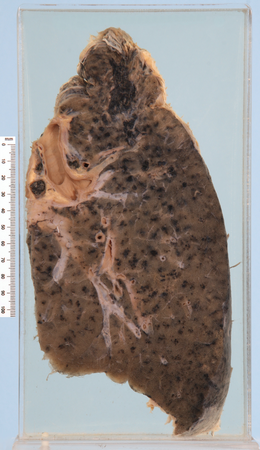

Emphysema, bullae

Anthracosis